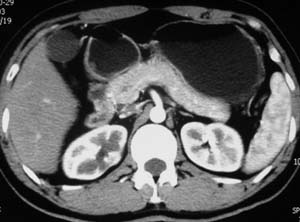

以下是引用子期在2010-3-19 20:47:00的发言:[br]血管畸形的ct增强应该有明显强化,本例并不相符合。本例双肾局部的略低密度影,累及肾盂,局部皮质明显变薄、内陷,增强扫描有轻度的强化,应考虑为炎性病变,患者为年轻男性,累及双肾的感染以结核较常见,可以没有明显的临床症状,尿中有时候也并不能查出什么;肾脓肿常有明显感染中毒症状,本例不符,另外一般的肾盂肾炎或肾小球肾炎通过小便就可确诊,其它还不能排除的是黄色肉芽肿性肾盂肾炎,然而单凭ct一般也很难鉴别。